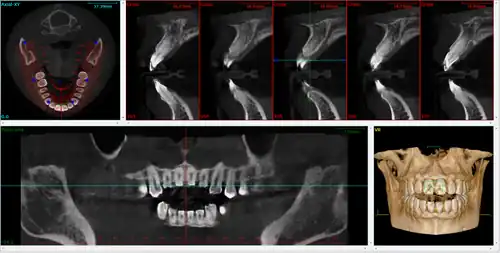

During dental/orthodontic imaging, the CBCT scanner rotates around the patient's head, obtaining up to nearly 600 distinct images. For interventional radiology, the patient is positioned offset to the table so that the region of interest is centered in the field of view for the cone beam. A single 200 degree rotation over the region of interest acquires a volumetric data set. The scanning software collects the data and reconstructs it, producing what is termed a digital volume composed of three-dimensional voxels of anatomical data that can then be manipulated and visualized with specialized software.[2][3] CBCT shares many similarities with traditional (fan beam) CT however there are important differences, particularly for reconstruction. CBCT has been described as the gold standard for imaging the oral and maxillofacial area.

A dental cone beam scan offers useful information when it comes to the assessment and planning of surgical implants. The American Academy of Oral and Maxillofacial Radiology (AAOMR) suggests cone-beam CT as the preferred method for presurgical assessment of dental implant sites.[20]

Orthodontics

As a 3D rendition, CBCT offers an undistorted view of the dentition that can be used to accurately visualize both erupted and non-erupted teeth, tooth root orientation and anomalous structures, that conventional 2D radiography cannot.[21]